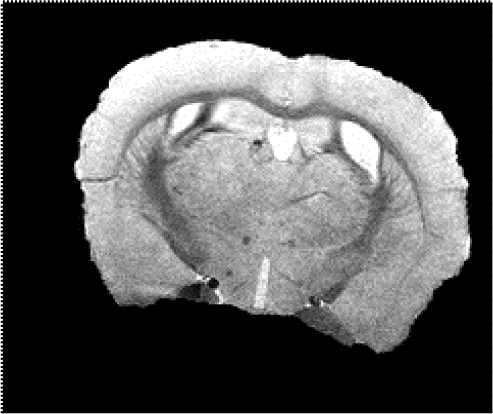

Figure 1. All fifteen mice survived the in-vivo imaging before being euthanized. Representative images of a control mouse and +/+ mouse at 12 months old are shown.